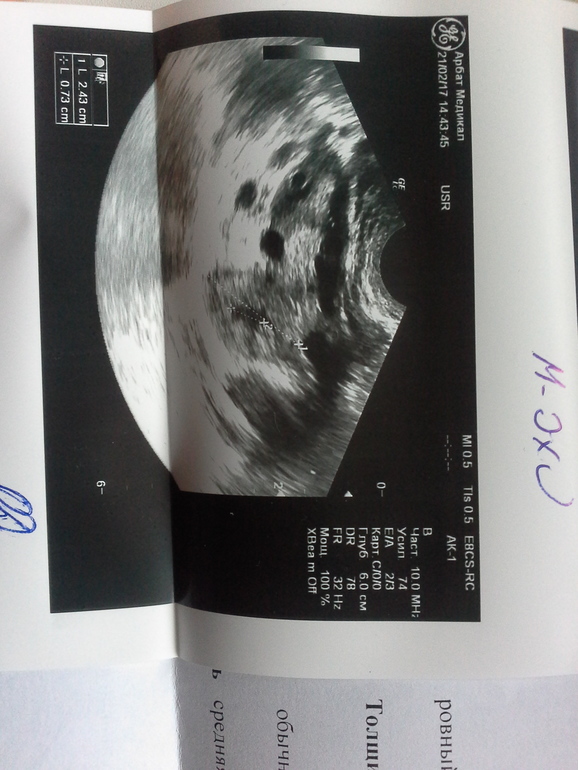

Сегодня сходила глянула чтож с температура не поднимается(( Нашли с моего пинка Узистке ЖТ 2.43см и внутренняя полость 0.74см. Эдометрий 1.29см жидкости в позадиматочном пространстве уже нет!

Кровоток еле еле просматривается((( она и сомневалась что это ЖТ из за этого! Может из за плохого кровотока и не поднимается температура?